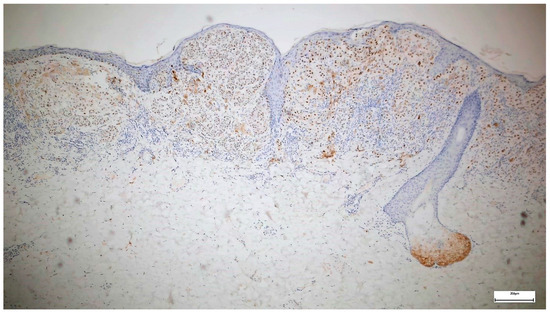

3. Results